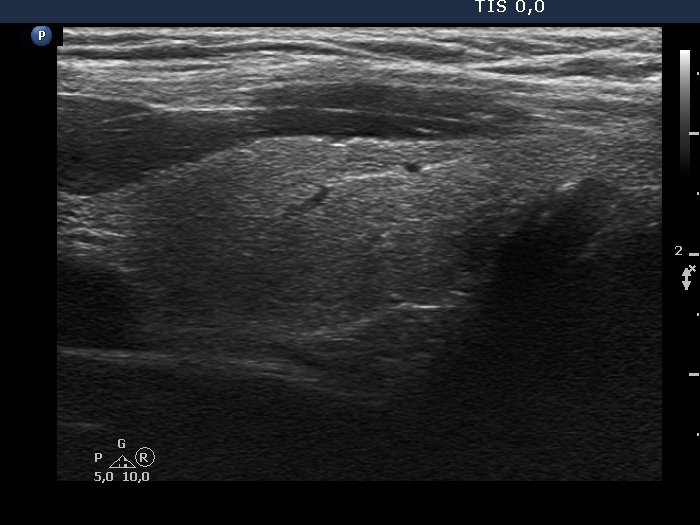

100 consecutive cases of papillary cancer - case 091 (ultrasonographic picture 6)

Left lobe, longitudinal scan.